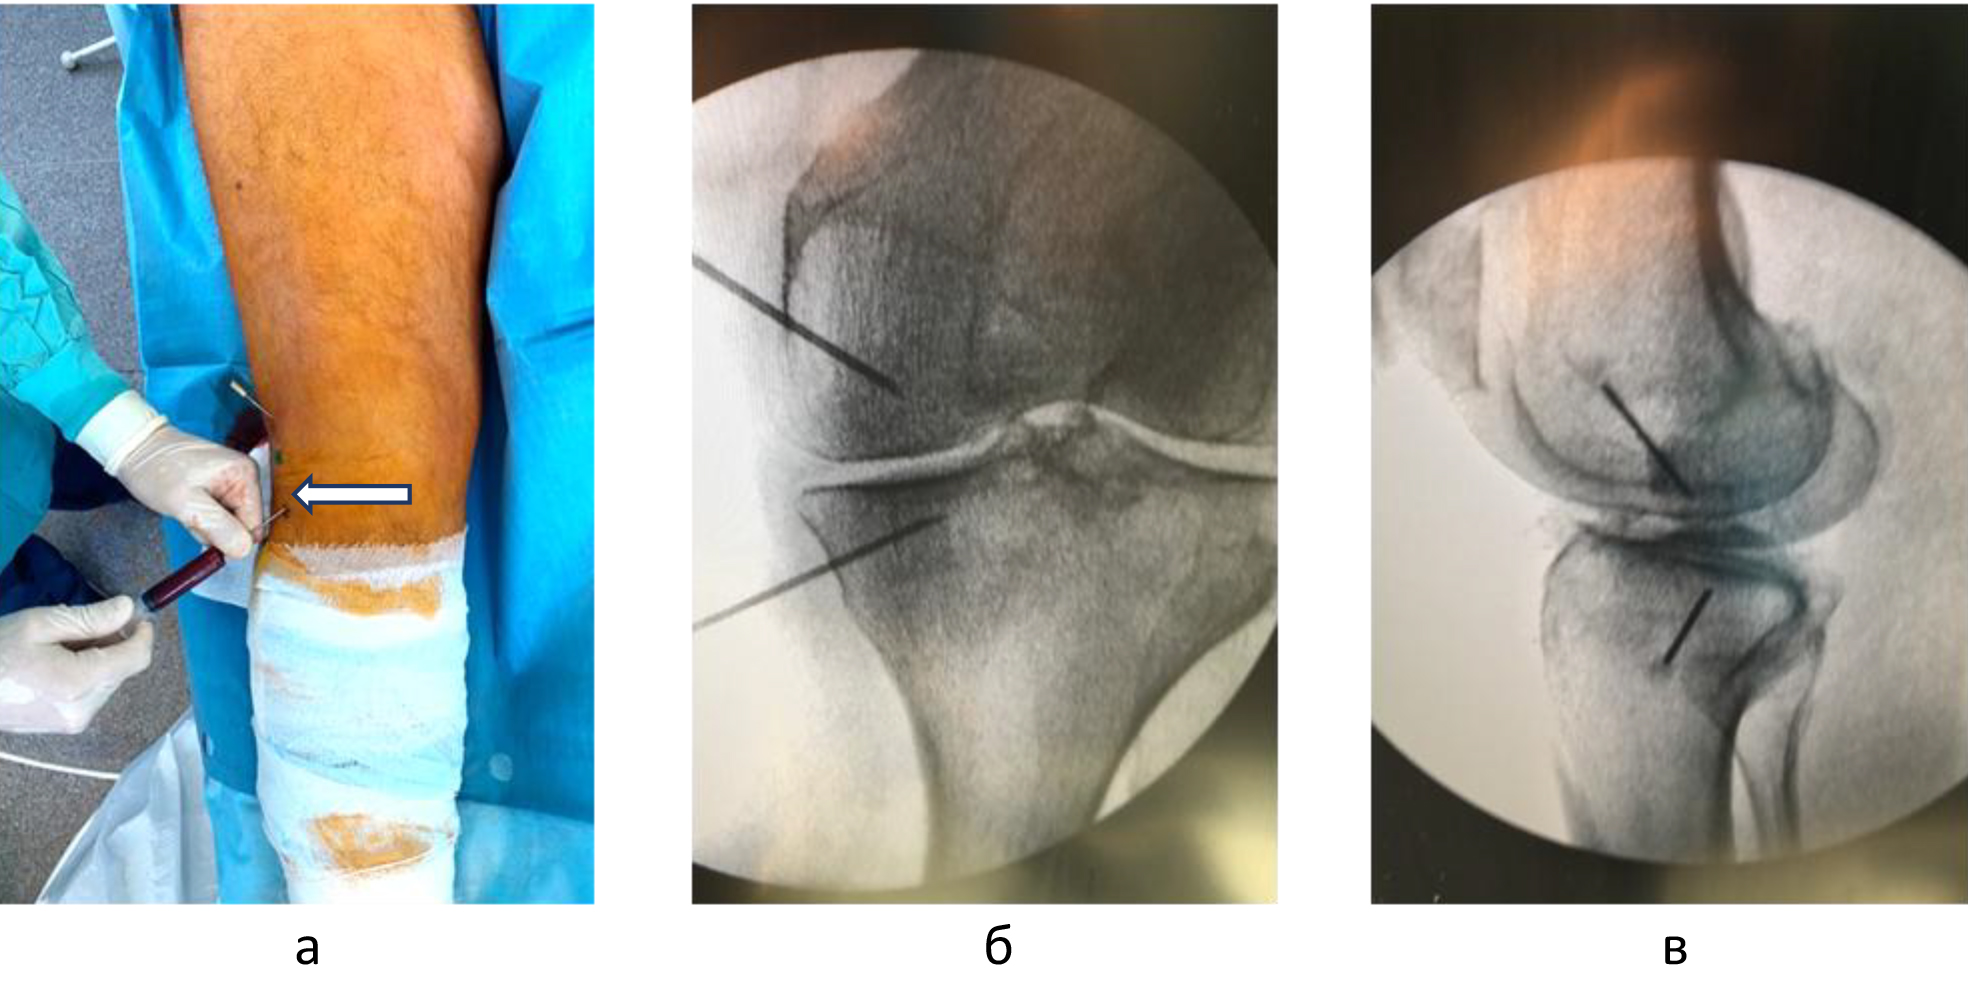

Для определения локализации и распространенности перегрузочного отека костного мозга всем пациентам выполняли МРТ. На Т1-взвешенных изображениях визуализировали снижение интенсивности сигнала, на Т2-взвешенных изображениях с жироподавлением и на коротких последовательностях «восстановления – инверсии» (STIR) выявляли высокую интенсивность сигнала (рис. 1).

Рис. 1. МРТ-картина трабекулярного отека костного мозга внутренних мыщелков бедренной и большеберцовой костей: a, б – T1-взвешенные изображения; в, г – T2-взвешенные изображения с подавлением жира